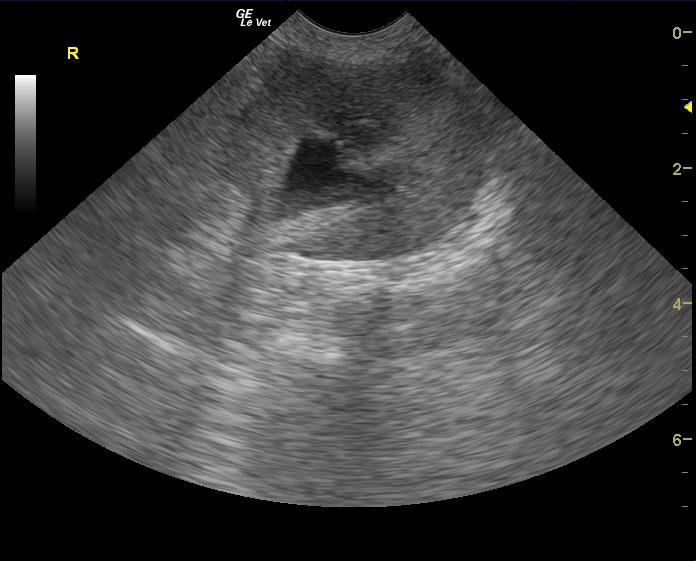

The patient is a feline DSH, SF, 17 years old. Clinical exam findings: Acute onset weakness and fever on PE (105 F), client reports hyperexia and acute onset stranguria, pollakiuria. Recently increased Methimazole due to ongoing elevation in T4. Recent COHAT with extraction, mild suture reaction, no intra-oral inflammation currently. History of suspected pyelonephritis treated with 6 week course Clavamox with 2 negative cultures. Altered CBC/Chem/UA values: Today- CBC- WBC= 24 (5.5-19), Lym= 1.26 (1.5-14), Neut= 21.4 (2.5-14). Chemistry: BUN= 57 , Creatinine= 3.4 (0.3-2.1). Systemic BP WNL.

The patient is a feline DSH, SF, 17 years old. Clinical exam findings: Acute onset weakness and fever on PE (105 F), client reports hyperexia and acute onset stranguria, pollakiuria. Recently increased Methimazole due to ongoing elevation in T4. Recent COHAT with extraction, mild suture reaction, no intra-oral inflammation currently. History of suspected pyelonephritis treated with 6 week course Clavamox with 2 negative cultures. Altered CBC/Chem/UA values: Today- CBC- WBC= 24 (5.5-19), Lym= 1.26 (1.5-14), Neut= 21.4 (2.5-14). Chemistry: BUN= 57 , Creatinine= 3.4 (0.3-2.1). Systemic BP WNL. U/A- U.S.G.= 1.020, NSF, sent out for culture. B/W performed a week ago- CBC WNL (WBC= 9, Neut= 5.8), Chemistry- BUN= 42, Creatinine = 2.2.